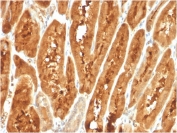

IHC staining of FFPE human liver carcinoma with FABP1 antibody. HIER: boil tissue sections in pH 9 10mM Tris with 1mM EDTA for 20 min and allow to cool before testing.